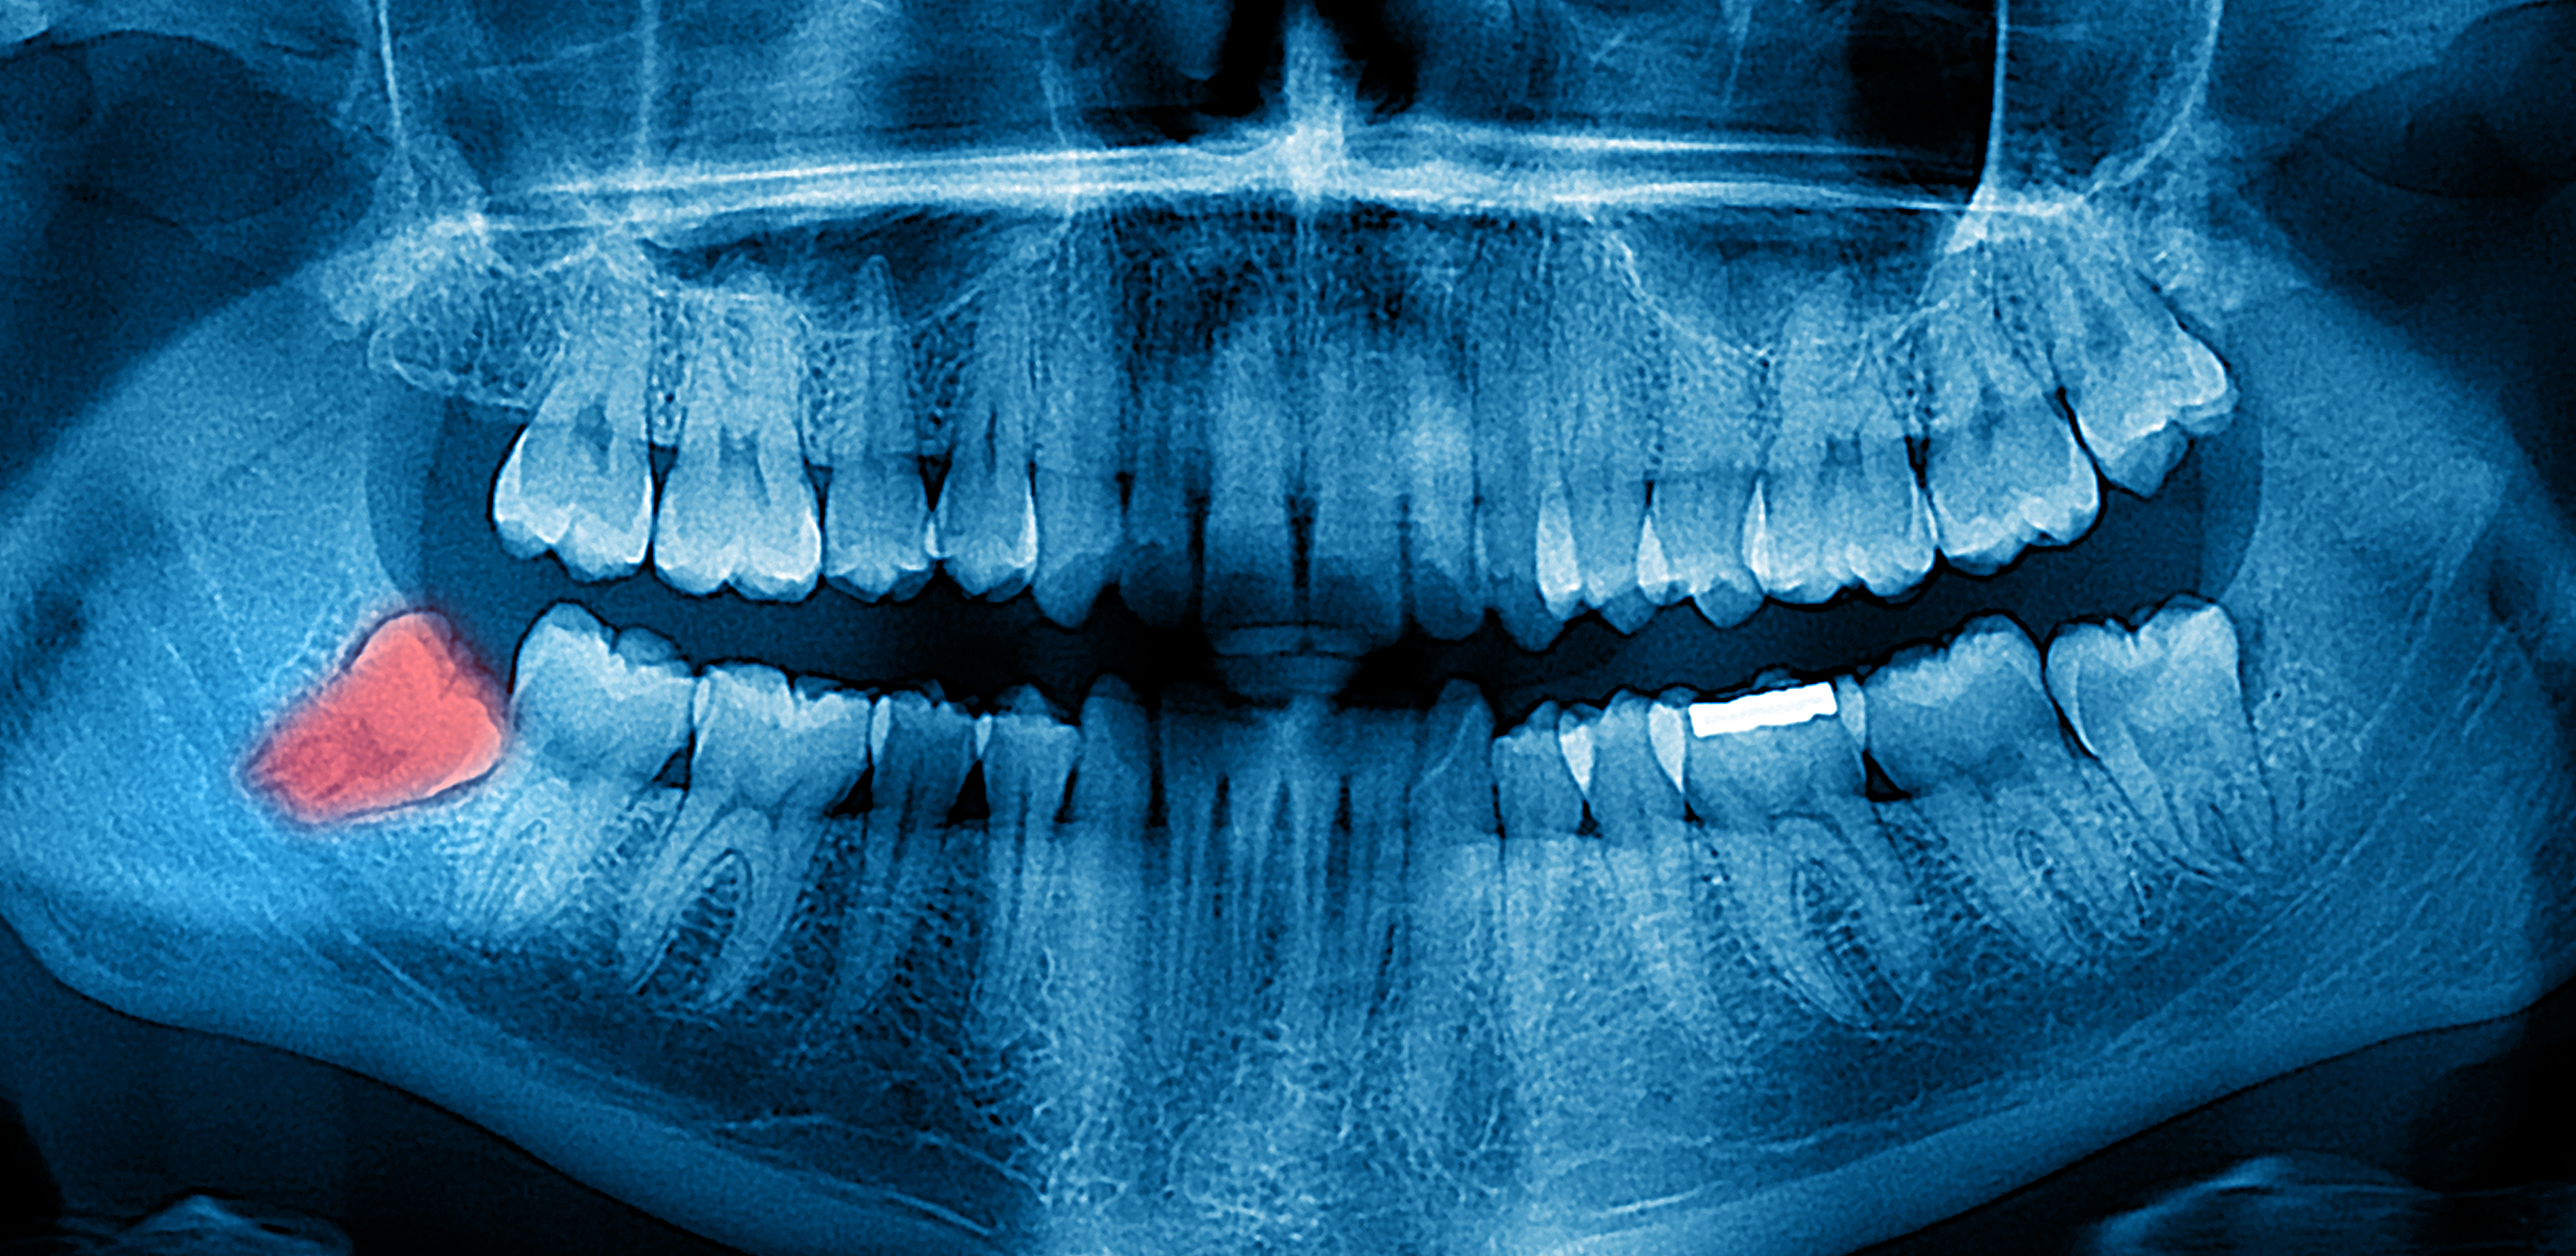

Dental X-rays are more than just tools for diagnosing cavities; they provide a comprehensive view of your oral health status. By allowing dentists to detect problems before they become severe, these images can save patients time, money, and discomfort in the long run. Early detection through modern imaging technology can reveal hidden decay between teeth, bone loss due to gum disease, or even cysts and tumors that are not visible during a standard exam.

- Impacted Teeth - Revealing teeth that are not properly erupting, such as wisdom teeth.

- Tumors - Spotting abnormal growths or cysts within the jawbone.

Despite the myths surrounding dental x-rays, they play an integral role in preventative dentistry. X-rays allow dentists to detect issues that are not visible during a standard oral exam. This includes early signs of decay between teeth, problems below the gum line, and changes in bone density that could indicate periodontal disease. By identifying these problems early, fundamental dental treatments can be administered promptly, saving patients from more extensive and costly procedures down the line.